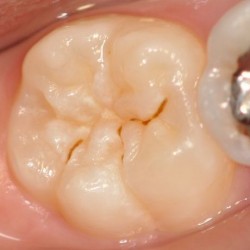

シーラント処置前

-

シーラント処置後

虫歯のなりかけであれば再石灰化と言われる歯の再生も見込めるので、むやみに歯を削らず、定期検診で歯の状態をチェックしていきます。